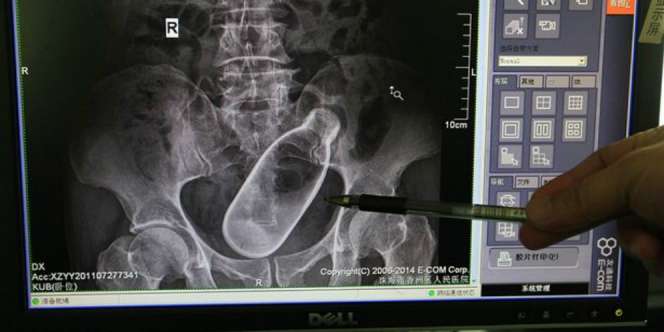

Foto Rontgen (Mirror.co.uk)

Dream - Foto rontgen yang dirilis rumah sakit di China mungkin bisa membuat bulu kuduk berdiri. Betapa tidak, foto itu menampilkan bagian anus seorang pria di mana sebuah botol tersangkut di dalamnya.

Pasien berusia 60 tahun dari Zhuhai, Provinsi Guangdong, China itu mengungkapkan, awalnya dia merasa sembelit dan mencoba merangsang dengan menggunakan botol.

Namun saat semua bagian botol masuk, dia tidak bisa mencabutnya keluar. Foto pria dengan botol di anusnya menjadi viral saat diunggah oleh orang-orang di rumah sakit.

Hingga berita ini diturunkan, belum diketahui apakah tim dokter bisa mengeluarkan botol tersebut.